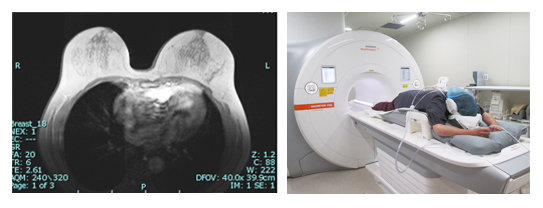

乳がんMRI検査:18,000円

乳がんを診断するための乳腺MRI(3.0テスラ検査)、最も病変発見率の高い画像診断です。放射線科専門医による結果説明があります。(後日金曜日)

※妊娠中の方、ペースメーカー挿入中の方はご相談ください。